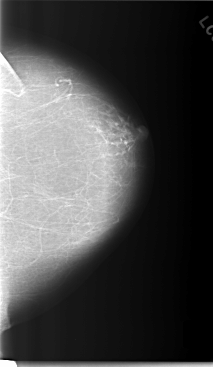

C_0236_1.RIGHT_CC

LEFT_CC LINES 5864 PIXELS_PER_LINE 3400 BITS_PER_PIXEL 12 RESOLUTION 50 NON_OVERLAY